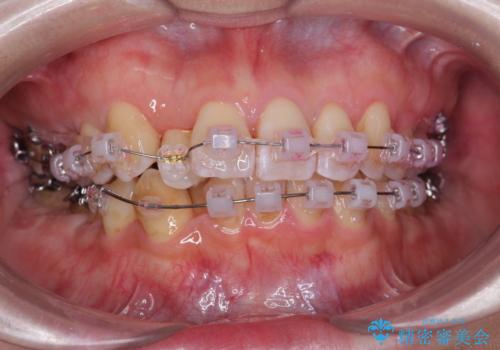

やや難ケース 上の歯を抜かずに歯列を後ろに下げて治療 4本ではなく下1本のみの抜歯できれいに

- 前歯のがたつき 歯並びを主訴に来院。

右の上下の混雑が激しく、通常は上下左右4本抜歯も相当する症状でした。

結果下の前歯一本抜歯ですみ、治療期間も想定よりも短く終わり、無事うまく治療することができました。

前歯の角度もよくなり、奥歯のかみ合わせも問題なく、上は非抜歯で口元も閉じやすくなりました。